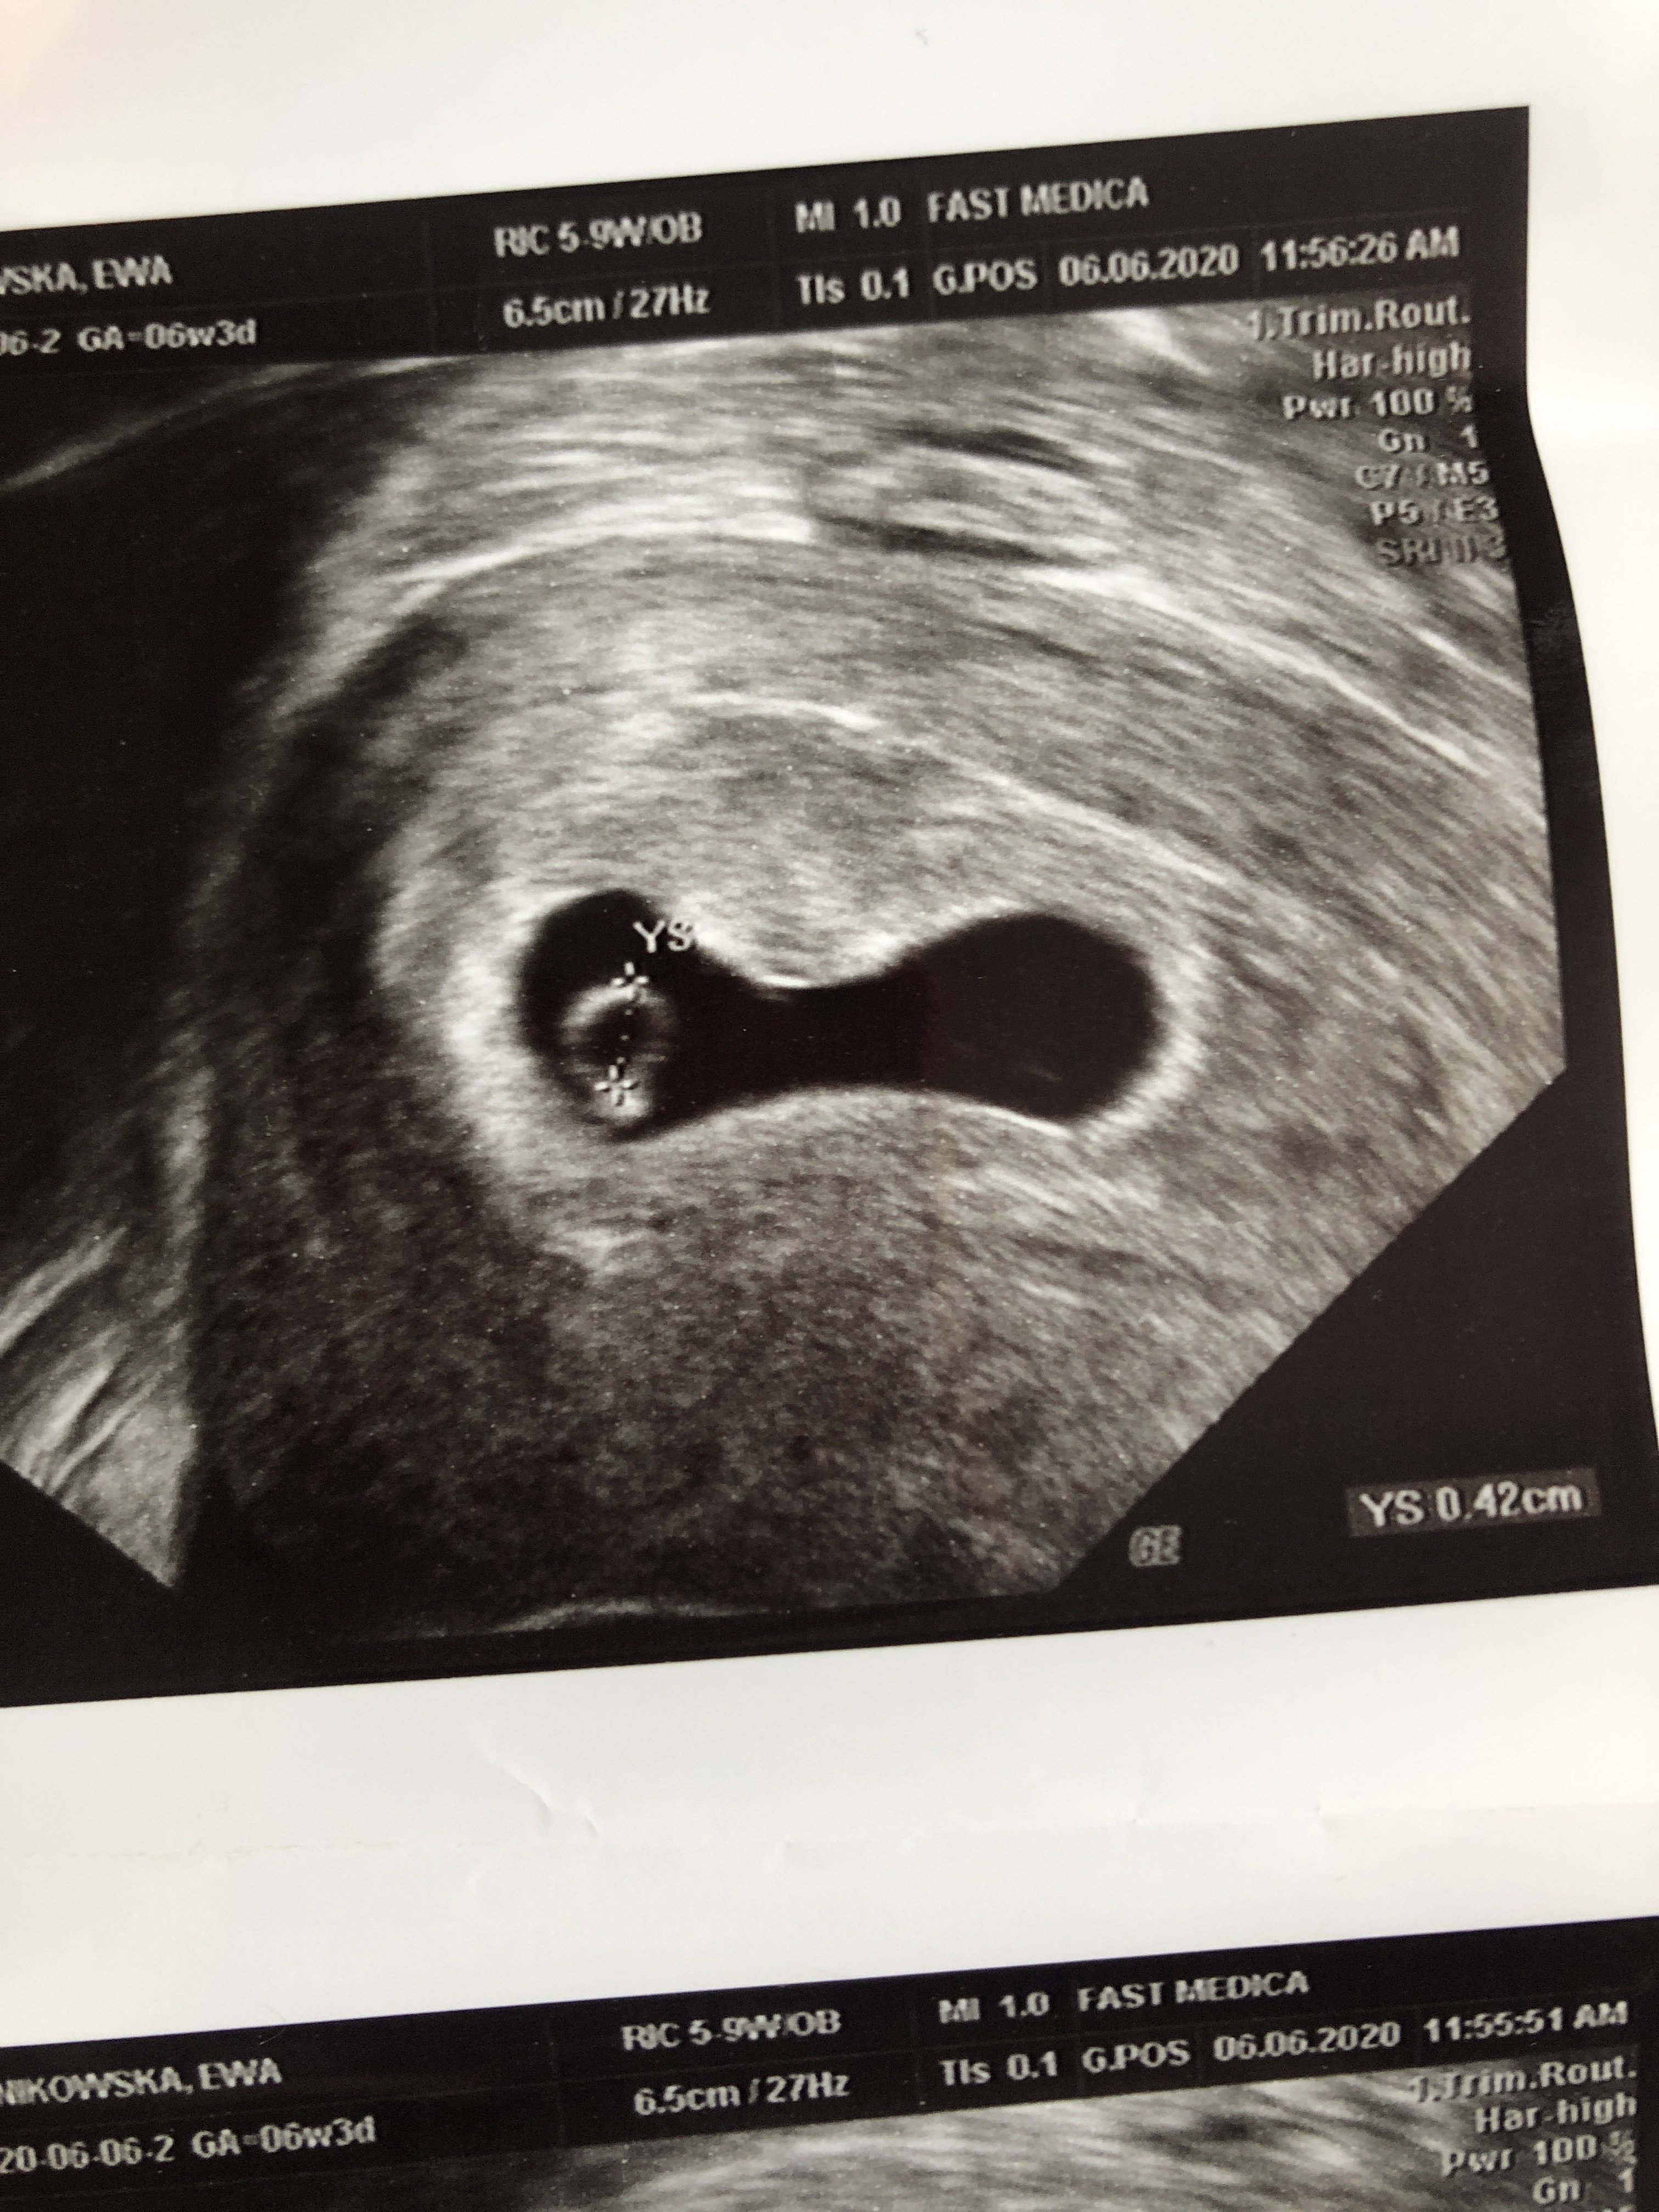

kochane ja już po wizycie dużo stresu według Om 6+3 według usg 6+1

termin porodu na 28 stycznia Srsduszlo bije ❤️❤️ Tylko pęcherzyk trochę spłaszczony dostałam leki na podniesienie progesteronu trochę się tym martwię 😔 i zalecił mi branie acard czy któraś tez bieze

termin porodu na 28 stycznia Srsduszlo bije ❤❤ Tylko pęcherzyk trochę spłaszczony dostałam leki na podniesienie progesteronu trochę się tym martwię 😔 i zalecił mi branie acard czy któraś tez bieze